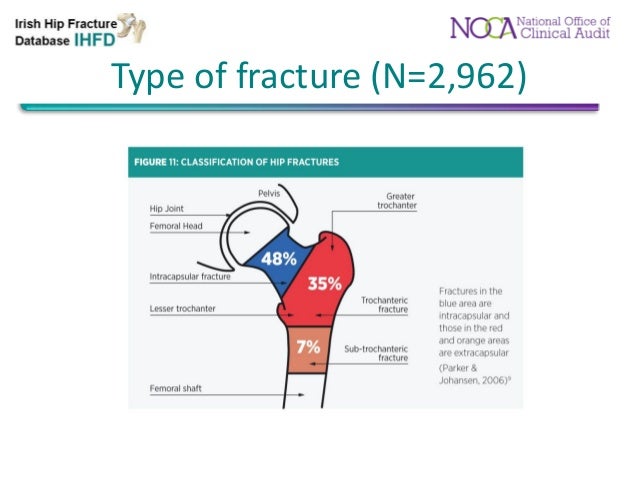

A hip fracture is a serious femoral fracture that occurs in the proximal end of the femur (the long bone running through the thigh), near the hip.